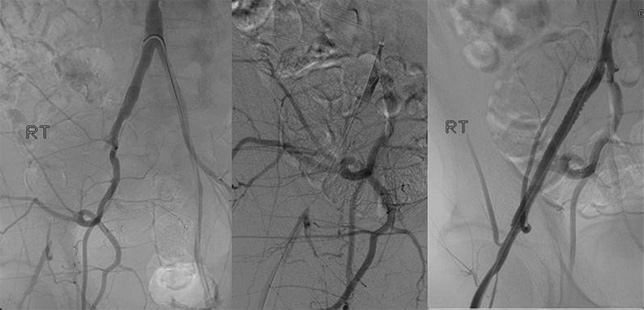

GENDER: Female

AGE: 62 years old

DEVICE: Wingman™

PHYSICIAN: Peter A. Soukas, MD, FACC, FSVM, FSCAI, FACP, RPVI

• Prior tobacco use, high blood pressure, hyperlimidemia, gastroesophageal reflux disease (GERD), hypothyroidism

• Presented with severe right calf claudication and right ABI of 0.5 duplex showing right popliteal occlusion

• Wingman™ catheter successfully crossed into anterior tibial enabling laser angioplasty

• Angiogram showing good result after percutaneous transluminal angioplasty (PTA) with drug-coated balloon (DCB) and stenting